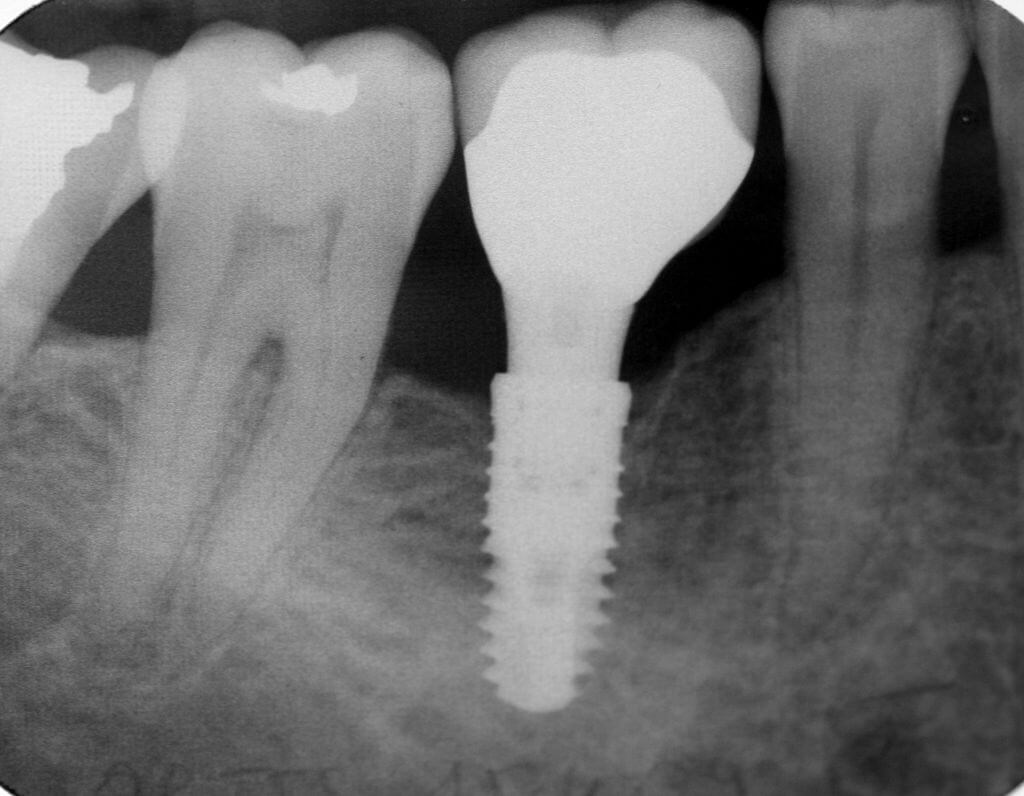

The surgical titanium dental implant is slightly larger than the hole made by the drill, this way the dental implant is held fast by the patients bone material. The dental implant is threaded, and can thus be screwed into the jawbone, and this is why ample bone material is necessary, and this is why you may need to have bone augmentation before you get your dental implant.

After the dental implant has been inserted, the gums will be sewn shut above the dental implant. There will be swelling of the area. which should subside within two to three days, and there should be no pain after the swelling is gone. One week after the surgery, your stitches will be removed, and you may be given a temporary crown as well.

At this point there are no visible portions of the dental implant, so the previous prostheses, such as dentures, bridges and crowns can be worn just as usual.During the following months, the bone will grow on to and through the dental implant itself, and once this process is done, you can book an appointment for an uncovering. During this time, the gum will be peeled back, and a healing screw will be inserted, along with a healing abutment. An impression will be taken of your teeth, and a crown will be made for your in a week or so.